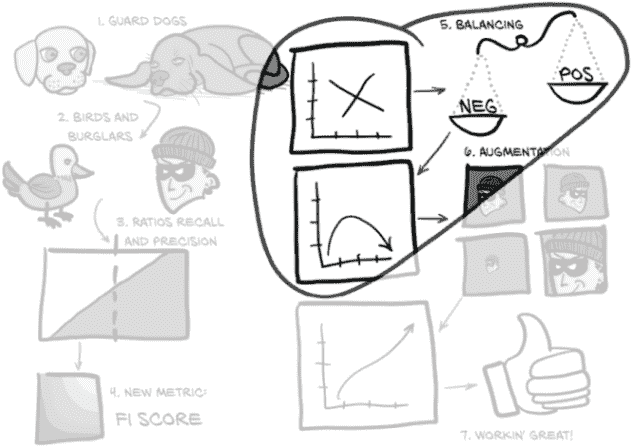

我们所看到的是过拟合的明显迹象。让我们看一下我们在正样本上的损失图,见图 12.18。

图 12.18 我们的正损失显示出明显的过拟合迹象,因为训练损失和验证损失趋势不同。

在这里,我们可以看到我们的正样本的训练损失几乎为零–每个正样本训练样本都得到了几乎完美的预测。然而,我们的正样本的验证损失却在增加,这意味着我们的实际表现可能正在变差。在这一点上,最好停止训练脚本,因为模型不再改进。

提示 通常,如果您的模型在训练集上的表现正在提高,而在验证集上表现变差,那么模型已经开始过拟合。

然而,我们必须注意检查正确的指标,因为这种趋势只发生在我们的正损失上。如果我们看一下我们的整体损失,一切似乎都很好!这是因为我们的验证集不平衡,所以整体损失被我们的负样本所主导。正如图 12.19 所示,我们在我们的负样本中没有看到相同的发散行为。相反,我们的负损失看起来很好!这是因为我们有 400 倍的负样本,所以模型要记住个别细节要困难得多。然而,我们的正训练集只有 1,215 个样本。虽然我们多次重复这些样本,但这并不会使它们更难记忆。模型正在从泛化原则转变为基本上记住这 1,215 个样本的怪癖,并声称不属于这几个样本之一的任何东西都是负样本。这包括负训练样本和我们验证集中的所有内容(正负样本都有)。

图 12.19 我们的负损失没有显示过拟合的迹象